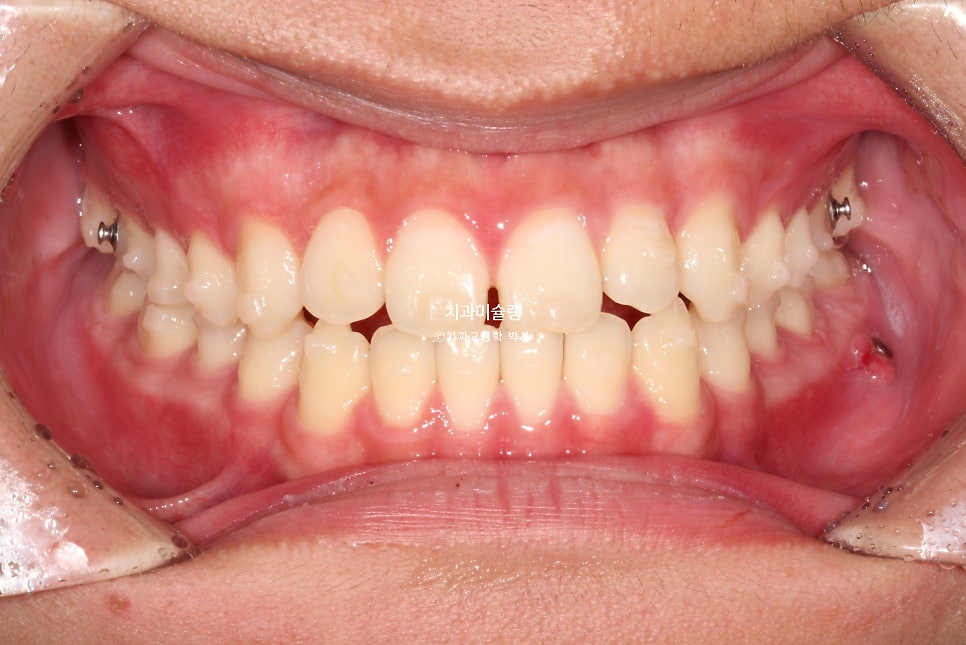

첫 세트 장치는 총 50개가 나왔습니다. 환자분은 장치를 들고 출국했다가 2025년 봄방학때 잠깐 들어와 중간 체크를 하고 다시 출국, 4달후 여름방학을 맞아 내원했을때 25번 장치를 끼고있던 모습입니다.

교정용 나사와 뺏다꼈다 하는 고무줄로 아래 어금니 후방이동을 도모하는 중입니다.

파란 화살표에 공간이 생긴만큼 어금니가 사랑니 공간으로 잘 이동했습니다.

앞니 교합은 좋아졌으며 중심선이 약간 아쉽습니다.

우측 교합관계는 1급을 달성했으나 좌측 교합관계가 아직 아쉽습니다.